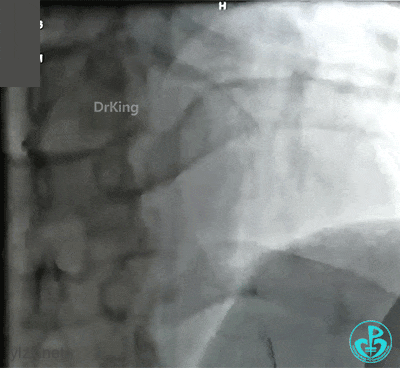

抽吸后前降支近段血栓消失,局部残留狭窄50%。患者胸痛缓解,拟择期复查造影。